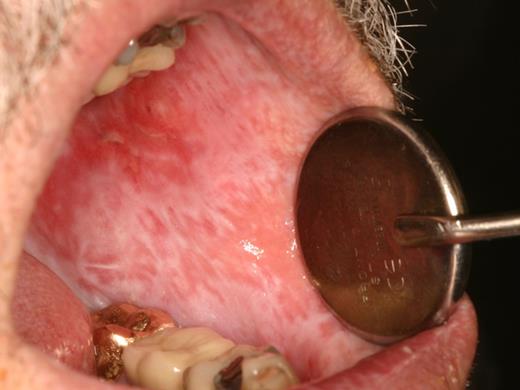

Oral mucosal cGVHD is characterized by lichenoid inflammation that can involve all intraoral sites, but particularly affects the tongue and buccal mucosa.8,13,14 Clinical signs include white hyperkeratotic reticulations and plaques, erythematous changes, and ulcerations, which can range from very limited disease with only mild reticulation to more extensive disease with painful ulcerations (Figures 1 and 2). Of note, the soft palate is infrequently affected, and cGVHD changes rarely extend posteriorly to the oropharynx (Figure 3).13 The lips are also a frequent site of involvement, demonstrating the same changes observed intraorally, and can be a source of significant discomfort (Figure 4).

cGVHD of the buccal mucosa with extensive multifocal areas of ulceration interspersed with erythema and reticulation.

The primary symptom associated with oral mucosal cGVHD is sensitivity to otherwise normally tolerated foods, drinks, and oral hygiene products, with most patients reporting little if any oral discomfort at rest. Foods and drinks that are consistently reported by patients as being painful include those that are spicy (eg, even a very small amount of pepper), acidic (eg, fruits, salad dressing), and hard/rough/crunchy; however, in some patients there is universal sensitivity such that oral intake becomes severely restricted. Although symptoms are generally worse with more severe clinical manifestations, this is not universally true, and patients with only reticular changes may be as or more symptomatic than patients with ulcerations.13 When there are prominent reticular changes affecting the buccal mucosa, patients may report a sensation of mouth tightness and a reduced ability to open the mouth (Figure 5). This should be differentiated from oral tightness because of primary sclerotic cutaneous cGVHD or secondary to mucosal scarring (see “Sclerotic disease”).

cGVHD of the buccal mucosa with extensive and thick hyperkeratosis making the mouth feel “tight” with limited opening.